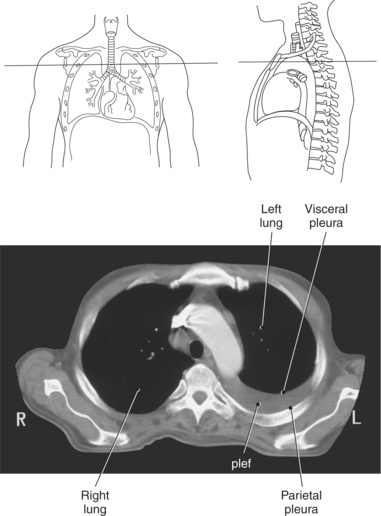

Each lung lies within a single pleural cavity that is lined by a serous membrane, or pleura. The pleura can be divided into two layers. The parietal pleura, the outer layer, is continuous with the thoracic wall and diaphragm and moves with these structures during respiration. The visceral pleura is the inner layer that closely covers the outer surface of the lung and continues into the fissures to cover the individual lobes as well. Both membranes secrete a small amount of pleural fluid that provides lubrication between the surfaces during breathing. Deep pockets or recesses of the pleural cavities are the costomediastinal and costodiaphragmatic recesses. The costomediastinal recesses are located at the point where the mediastinum and costal cartilages meet anteriorly, and the costodiaphragmatic recesses are located where the diaphragm and ribs connect inferiorly. These recesses serve as expansions to provide additional pleural space where parts of the lung can glide during inspiration (Figure 6.10 and 6.17).